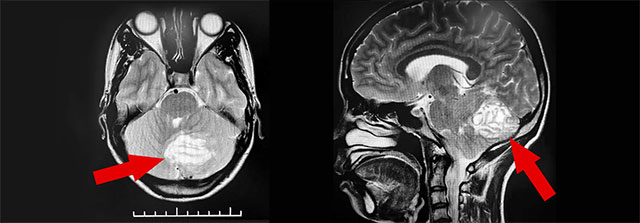

雖然屬于相當(dāng)少見的疾病,但小腦發(fā)育不良性神經(jīng)節(jié)細胞瘤較易獲得明確診斷。沈教授表示,小腦發(fā)育不良性神經(jīng)節(jié)細胞瘤的主要檢查方法是磁共振成像(MRI),MRI能清楚顯示小腦發(fā)育不良性神經(jīng)節(jié)細胞瘤的條紋狀或分層狀改變表現(xiàn),即所謂的“虎紋征”——這對小腦發(fā)育不良性神經(jīng)節(jié)細胞瘤具有術(shù)前定性診斷價值。

▲ MRI檢查顯示,該小腦腫瘤有明顯的“虎紋征”